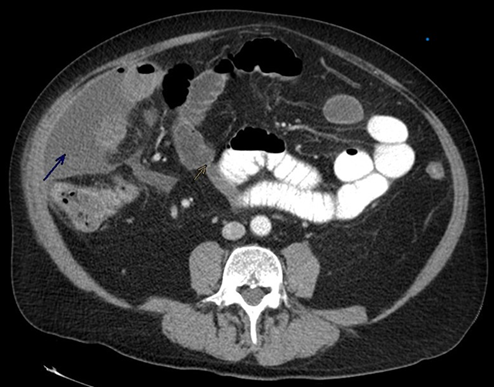

twice daily. Initial imaging with CT abdomen/pelvis

without contrast demonstrated narrowing of the ascending colon, possibly due to

the presence of a mass. Surrounding layering free fluid with a few small foci

of air within a collection measuring approximately 5.1 x 10.8 x 16.3 was

demonstrated, as seen in (Figure 1)

below.

Figure 1. Computed Tomography of

Abdomen with contrast. Blue Arrow pointing to layering free fluid foci with

apical pockets of air surrounding the ascending colon and yellow arrow pointing

to the stricture caused by the cancer.